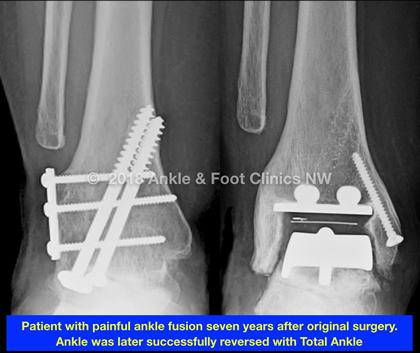

Ankle fusion reversal is a procedure that is becoming more and more common place to perform. In the past it was reserved for patients who had a poor response to ankle fusion including:

Delayed Fusion Reversal

A newer technique; this is a staged fusion reversal for younger patients, where the ankle is fused with the understanding that the patient will perform a reversal when they are older and less active. Arthroscopic fusion is an excellent way to fuse an ankle without destroying the gutter facets of the ankle joint which improves the success of fusion reversal. This technique is particularly important in patients with end stage ankle arthritis who are under 30 years old.